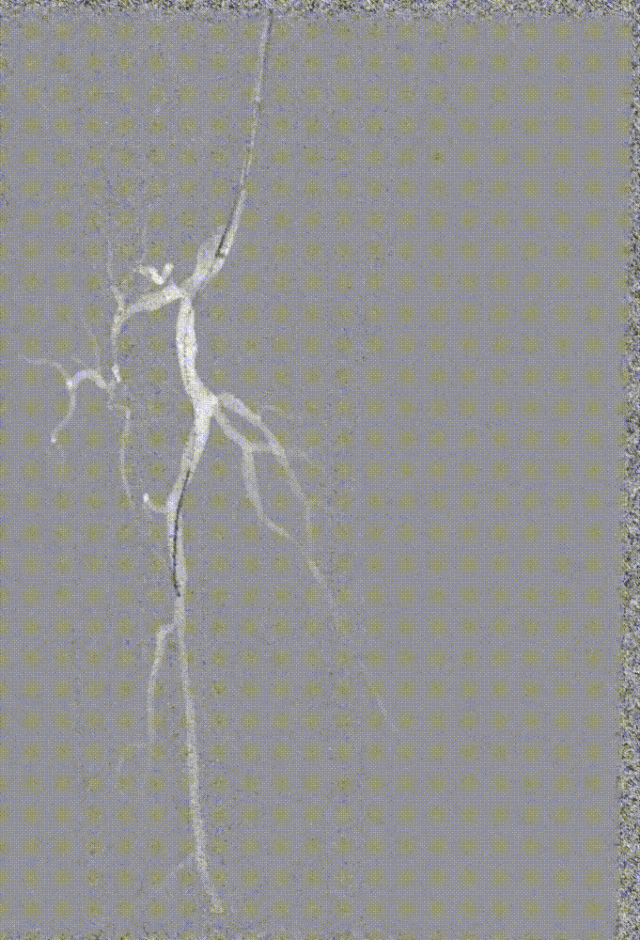

步进造影:股浅动脉起始重度狭窄、中段重度狭窄,腘动脉远端重度狭窄、胫前动脉、胫后动脉闭塞

V-18导丝配合多功能导管通过股浅动脉、腘动狭窄闭塞段,交换0.14导丝远端置于腓动脉中段

经导丝送入IVUS导管,股浅动脉近段重度狭窄、钙化明显,狭窄率大于90%

股浅动脉中远段及腘动脉重度狭窄、环周钙化明显